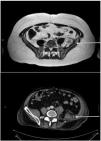

Plexus-neuropathy due to ilio-psoas hematoma in 4 COVID patients

Plexo-neuropatía por hematoma en iliopsoas en 4 pacientes COVID